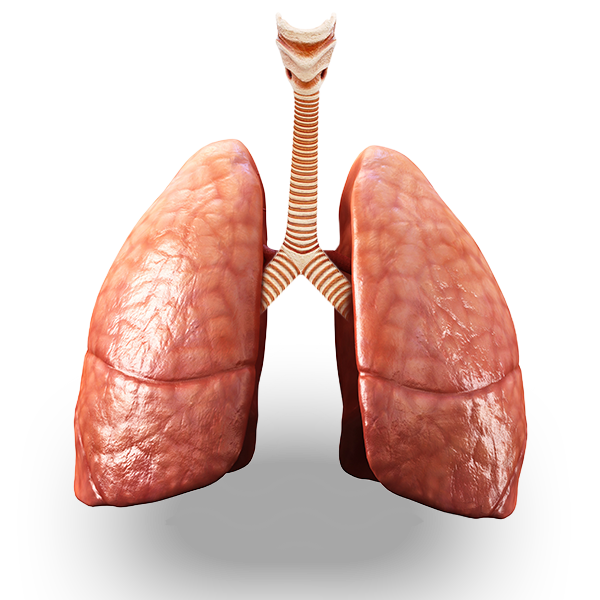

WEAKENED FROM THE INSIDE

Vaping can damage your body’s natural ability to defend itself.

WHAT CAN VAPING CAUSE?

The more studies they do, the more harms are exposed. Click to see health damage connected to vaping.